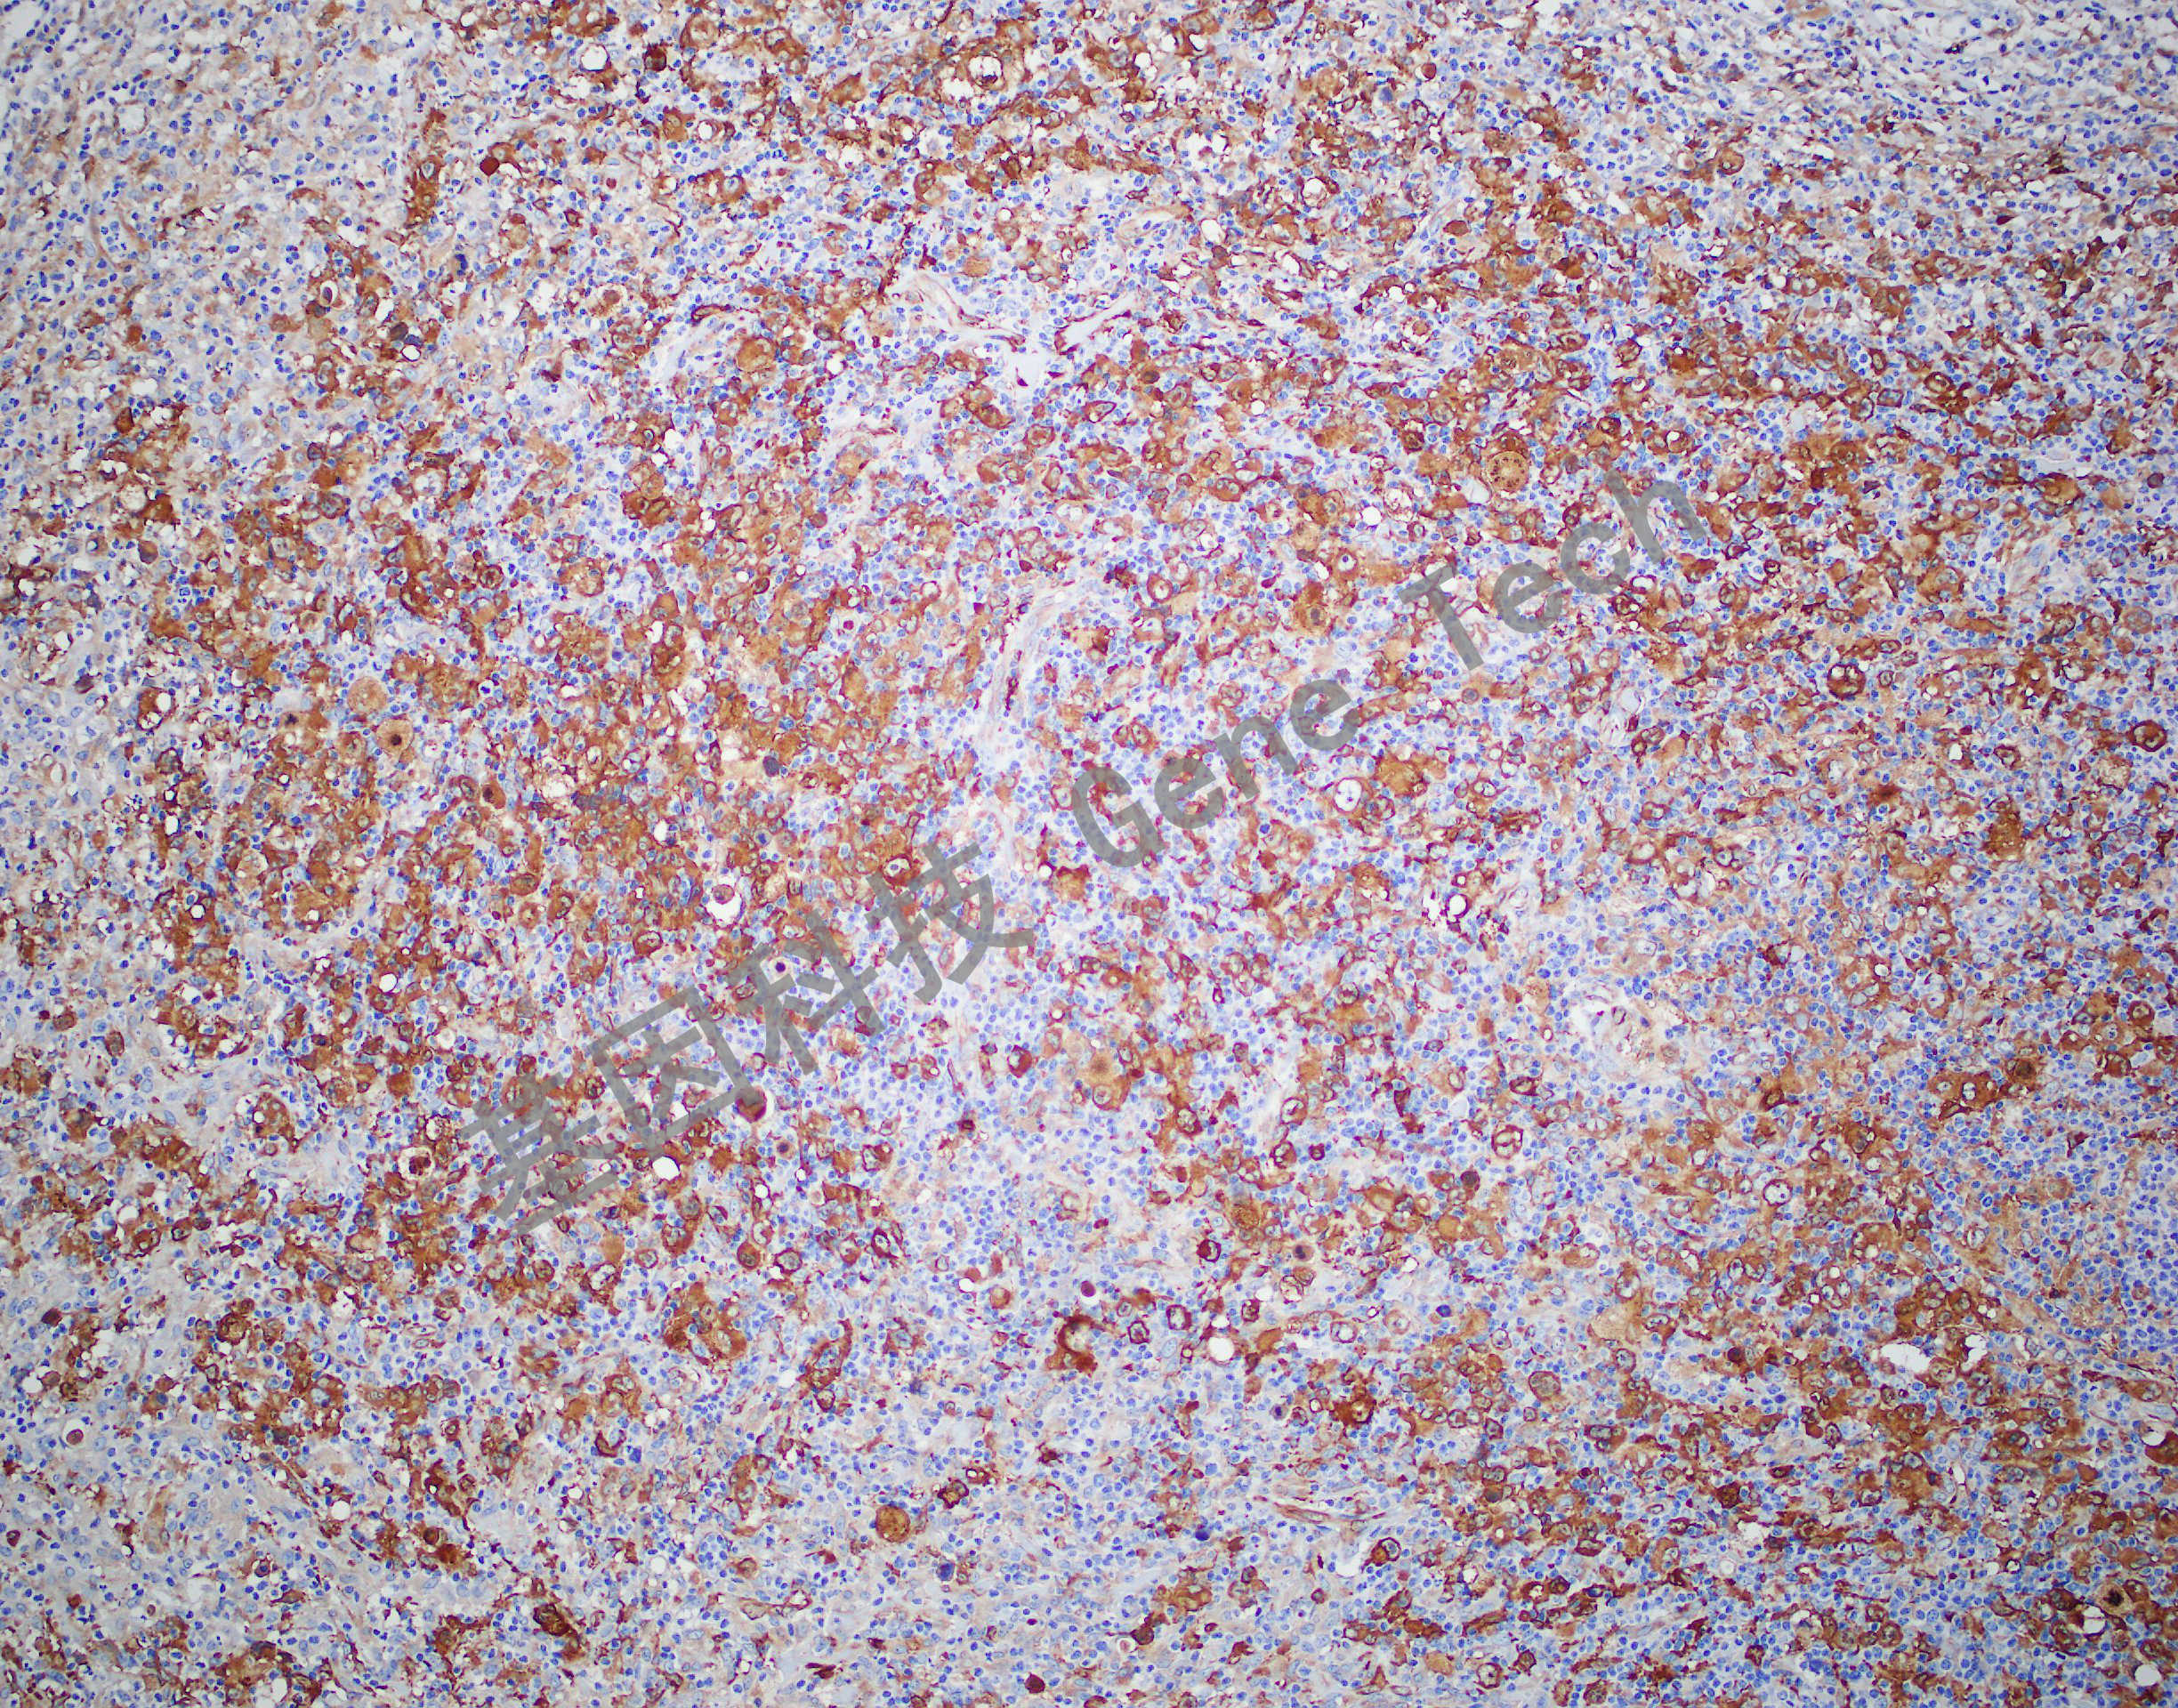

| 簡介:Fascin是由人同源的sn基因編碼的一種分子量為55kDa的蛋白,與有絲分裂中微絲的形成有關(guān)。在正常組織中,主要表達(dá)于各種樹突狀細(xì)胞和淋巴竇內(nèi)皮細(xì)胞。此外,Fascin在霍奇金淋巴瘤的R-S細(xì)胞中通常表達(dá)陽性。該抗體主要用于霍奇金淋巴瘤的診斷。 | ||

| 霍奇金淋巴瘤石蠟切片,用 Fascin(GM3567)染色,細(xì)胞漿陽性,DAB 顯色。 | ||